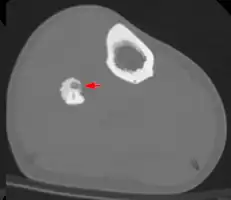

Radiographs in osteoid osteoma typically show a round lucency, containing a dense sclerotic central nidus (the characteristic lesion in this kind of tumor) surrounded by sclerotic bone. The nidus is seldom larger than 1.5 cm.

The lesion can in most cases be detected on CT scan, bone scans and angiograms. Plain radiographs are not always diagnostic. MRI adds little to the CT findings which are useful for localisation. Radionuclide scanning shows intense uptake which is useful for localisation at surgery using a hand held detector, and for confirmation that the entire lesion has been removed.[8][9]

2. CT scan showing an osteoid osteoma of the fibula with a clearly visible nidus

Nidus demonstrated by high resolution CT